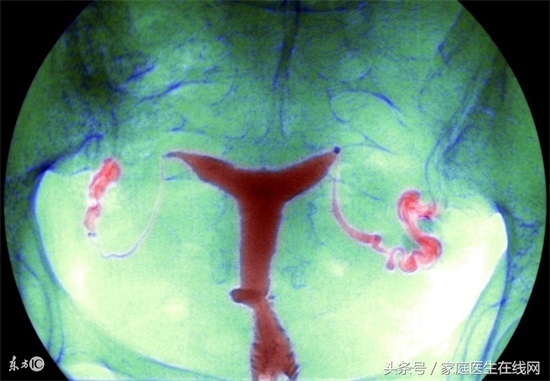

很多女性在做B超检查的时候,都会检出有少量盆腔积液,大多数的时候,医生都会说这事正常的,不用理会。从盆腔的解剖结构来看,子宫直肠窝处于盆腹腔的最低点,俗话说:水往低处流,所以只要盆腔有液体,就会因重力作用聚于此,而且哪怕少至两三毫升的液体积聚,在B超下都可以被检测出来。可是,有些情况的盆腔积液是需要治疗的,什么时候需要治疗呢?

专家表示,在每个月的排卵期,卵泡破裂后卵泡液流到盆腹腔,这时行B超检查也会提示子宫直肠窝少量积液。此外,月经期间少许经血逆流入腹腔,也可致少量的盆腔积液。

可见,少量的子宫直肠窝积液多为正常生理现象,不需对此过分担心,先看看B超的检查时间是否处于月经期或排卵期,必要时复查。一般生理性的盆腔积液都是可以自行吸收的,不必进行治疗,更不要盲目地就服用抗生素或某些清热祛湿的中成药,以免造成抗生素或药物的滥用。

少量盆腔积液不等于患上盆腔炎。正常人体内也有一定的盆腔积液,如果盆腔积液小于1公分以下还是正常的,但如果盆腔积液量多,就一定要去医院做详细检查,因为不止盆腔炎,其他疾病同样也有积液的可能。

如果B超显示积液量较多、范围较大,且伴有单侧或双侧腹痛、腰骶部疼痛、腰酸下坠、胀痛等症状,就要警惕是否为盆腔炎了。